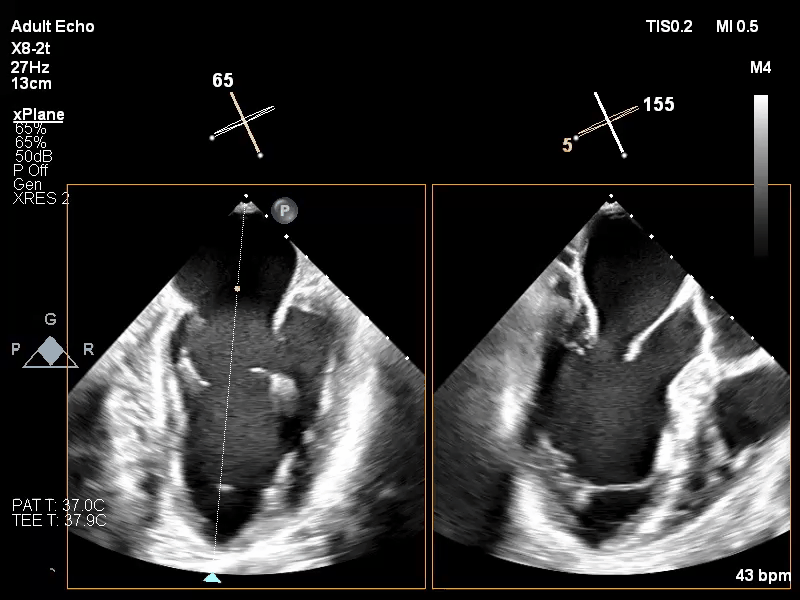

术前TEE XPLANE

经食道超声心动图(TEE)提示:二尖瓣病变Carpentier II型,DMR,二尖瓣2区反流及P2腱索断裂并瓣叶脱垂,Gap 6 mm,Width 15 mm, 瓣口面积6.7 cm²,2区前叶长20 mm,后叶长19 mm。MR4+,反流束来自于2区,偏心性反流束,指向前叶;VC 11 mm。房间隔穿刺空间约4.5 cm。